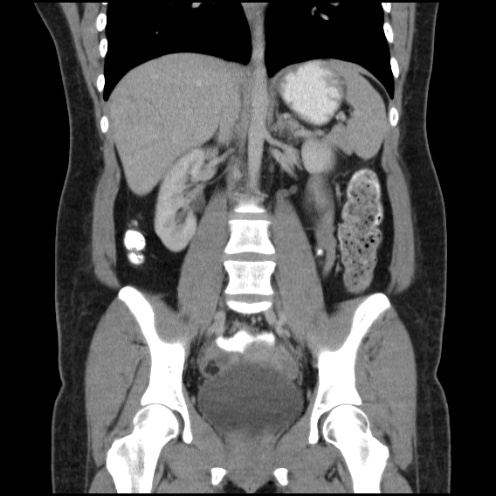

Paciente de 72 años con antecedente de tuberculosis genitourinaria hace 40 años.